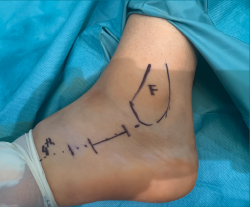

Para realizar el abordaje del seno del tarso(13) se sigue una línea imaginaria que discurre desde el eje del cuarto metatarsiano hasta la punta del maléolo lateral, realizando una la incisión de 2-3 cm sobre esta línea (se puede ampliar la incisión tanto hacia proximal como a distal) (Figura 1). La disección se debe realizar con cuidado para no dañar el nervio sural ni a los tendones peroneos que cruzan la incisión (Figura 2). Finalmente, se debe abrir el ligamento peroneo-calcáneo para acceder a la articulación subastragalina posterior; este paso no ha demostrado provocar inestabilidad de tobillo durante la evolución posterior.

Figura 1. Abordaje del seno del tarso de 2-3 cm. Se realiza una línea que va desde el cuarto metatarsiano (4th) al peroné. F: fíbula.